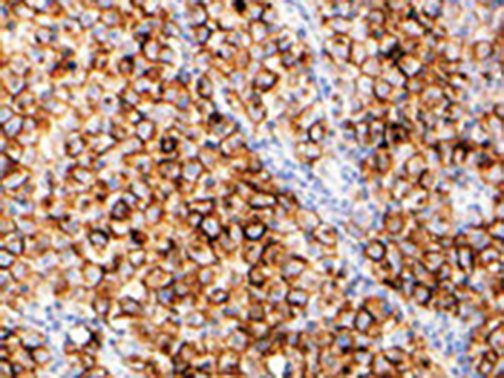

It is the ICU physician who is most likely to witness one of the deadliest manifestations of the abnormal immunological response, the cytokine storm syndrome (CSS). This response is also referred to by some as the cytokine release syndrome (CRS). CSS is characterized by continuous activation and expansion of macrophage and lymphocyte populations, which secrete large amounts of cytokines, causing the cytokine storm. This massive cytokine release is akin to hemophagocytic lymphohistiocytosis (HLH) disease, a syndrome characterized by initial unchecked and persistent activation of cytotoxic T lymphocytes and NK cells.

Clinical and laboratory manifestations of HLH include fever, enlarged liver and/or spleen, neurologic dysfunction, coagulopathy, liver dysfunction, cytopenias (i.e., low levels of erythrocytes, leukocytes, and/or platelets), hypertriglyceridemia, hyperferritinemia, hemophagocytosis, and eventually diminished NK cell activity as the immune system becomes progressively paralyzed. HLH can be familial (primary HLH) or secondary to another disease process (sHLH), such as rheumatic disease, in which it is referred to as macrophage activation syndrome (MAS, characterized by elevated ferritin).